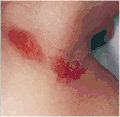

SymptomsDuskiness of face, facial petechia, bleeding in the whites of the eye[1]

A nuchal cord is a condition in which the umbilical cord becomes wrapped around the fetus's neck.[1] Symptoms present in the baby shortly after birth from a prior nuchal cord may include duskiness of face, facial petechia, and bleeding in the whites of the eye.[1] Complications can include meconium, respiratory distress, anemia, and stillbirth.[1] Multiple wraps are associated with greater risk.[3]

Symptoms of a prior nuchal cord shortly after birth in the baby may include duskiness of face, facial petechia, and bleeding in the whites of the eye.[1] Complications can include meconium, respiratory disease, anemia, and still birth.[1]